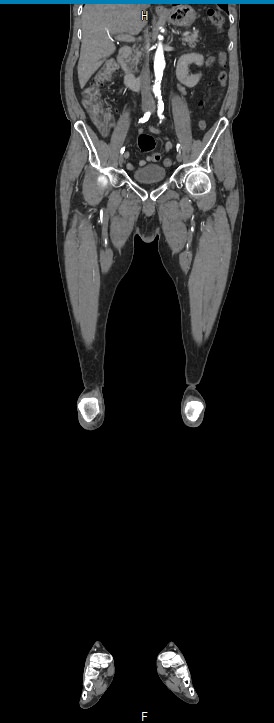

Назад КТ брюшного отдела аорты и сосудов (артерий) нижних конечностей

Основные показания для проведения КТ брюшного отдела аорты и артерий нижних конечностей могут включать:

• Аневризмы: оценка и диагностика аневризм брюшной аорты.

• Стенозы и окклюзии: выявление и оценка степени сужения или блокировки артерий.

• Тромбозы: обнаружение тромбов и оценка их размера и локализации.

• Атеросклероз: определение степени и распространенности атеросклеротических изменений.

• Подготовка к хирургическим вмешательствам: планирование сосудистых операций и вмешательств.

• Оценка послеоперационного состояния: контроль за состоянием сосудов после хирургических вмешательств.

Преимущества КТ брюшного отдела аорты и артерий нижних конечностей включают:

• Высокая точность и детализация изображений.

• Быстрота выполнения исследования.

• Возможность трехмерной реконструкции сосудов.

В целом, КТ брюшного отдела аорты и артерий нижних конечностей является эффективным методом диагностики сосудистых заболеваний и играет важную роль в планировании лечения и оценки его результатов.